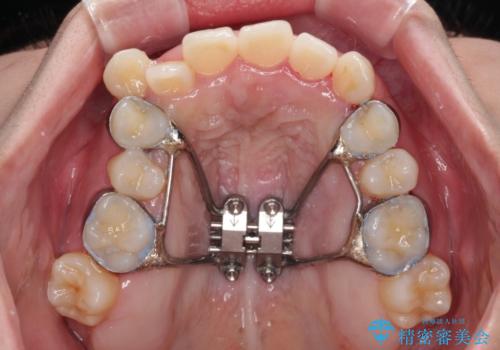

上顎歯列が下顎の歯列に対して狭小であり、一部下顎の奥歯が上顎よりも外側に位置している状態でした。

上顎の急速拡大装置を使用して上顎骨を側方に拡大することで上顎歯列を拡大し、下顎歯列も拡大できるようにすることで、歯列を整えることとしました。

歯列矯正では基本的に骨格を改善することはできませんが、急速拡大装置(MARPE)を使用することで上顎骨を側方に拡大させることができ、咬合状態を大きく改善することができます。